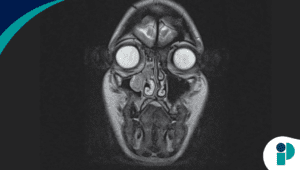

- ¿El virus se puede confundir con otras infecciones?

- Verdadero. Las lesiones en la piel causadas por el Mpox pueden confundirse con otras infecciones, como herpes, culebrilla, sífilis o varicela, entre otras.